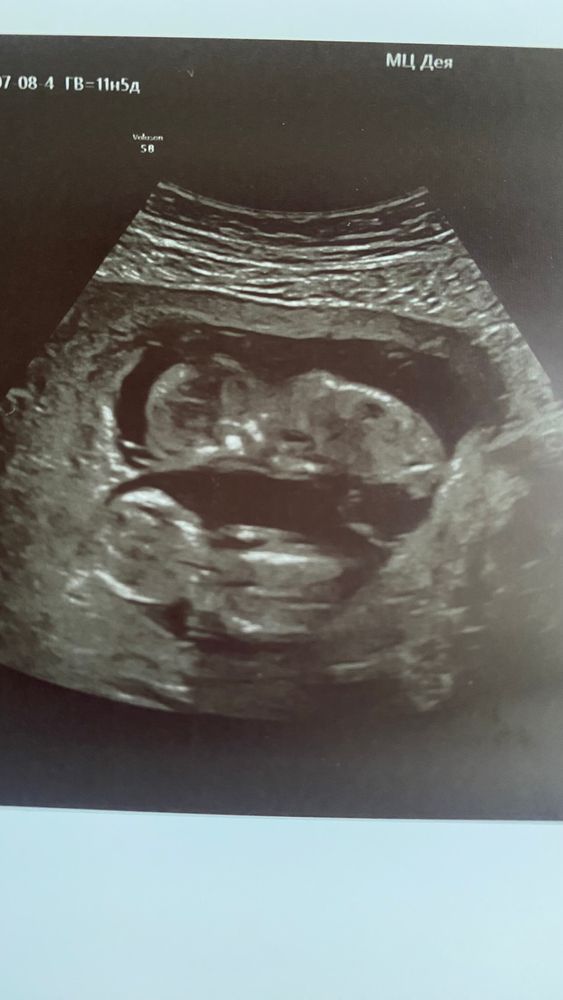

Первый скрининг, двойня ☺️

Всё отлично у нас! Развитие на 12 недель и 12 недель 1 день, всё на своих местах в нужных размерах.

Меня беспокоил кровоток, но он не изменён) шейка 38, зёв закрыт.

Прикрепление обоих по передней стенке, живот уже такой приличный я б сказала, а что дальше будет🙈

Пол ещё рано, подождем 2 скрининга или чуть раньше)